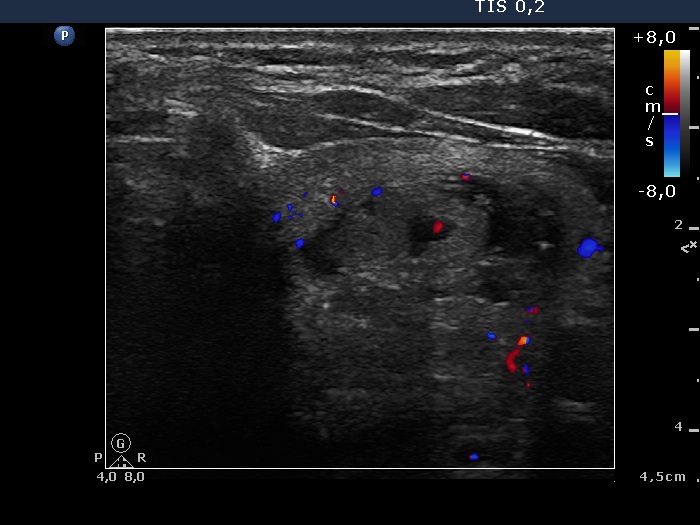

Right lobe, longitudinal scan

Left lobe, transverse scan, color Doppler mode. The lesion has intranodular vascularization.